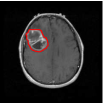

The relevance of tumor shape in characterizing tumor heterogeneity is linked to its growth process. Intrinsic brain tumors tend to evolve along tracts of white matter, altering the tracts in complex ways that include infiltration, displacement and disruption (Goldberg-Zimring et al., 2005). It is conceivable that new insight into patterns of tumor growth and invasion in the brain can be obtained through a better understanding of the shape and evolution of the tumor. Tumor shape is significantly influenced by the location in the brain and other anatomical constraints—in some places it might infiltrate and in others displace the fiber tracts. Irregular or spiculated shapes suggest an anisotropic structure of the underlying white matter; spherical or regular shapes imply a lack of structural or anatomical restrictions. The size of the tumor evidently affects its shape, especially in the presence of anatomical restrictions. It is reasonable to theorize that a better understanding of the relationship between the tumor’s shape and size, and histopathological factors related to the brain tumor would enhance the understanding of the tumor’s biological growth process; this would not only enable better prognosis but also potentially predict the likelihood of therapeutic success. For example, Figure 1 of our motivating dataset shows two semi-automated segmentations of T2-weighted fluid-attenuated inversion recovery (FLAIR) brain-axial MRI of patients diagnosed with glioblastoma multiforme (GBM), also known as grade IV glioma, with survival times of longer than 50 months (left) and shorter than one month (right), respectively. The tumor shape for the patient with longer survival appears to be more regular or spherical than the irregular one corresponding to the patient with a short survival; the tumor sizes appear to be quite different as well. Evidently, the tumor locations for the two patients are different, which influences both size and shape.

![]() |